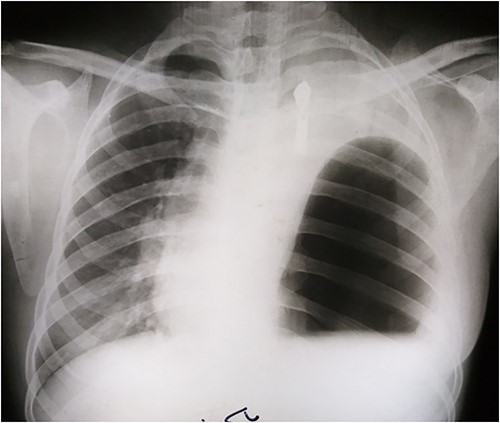

Laboratory tests showed white blood cells count of 9000/microliter with neutrophils 82%, mild anemia (Hb = 10 g/dl) and respiratory alkalosis (pH = 7.46, pCO2 = 28, and HCO3 = 20). Chest x-ray (CXR) of the chest was not able to visualize the left hemidiaphragm with a hollow viscus in the left thoracic cavity and a right shift of the mediastinum (Fig. 1). Computed tomography (CT) scan showed several viscera in the left thoracic cavity, containing air-fluid levels with the fluid not being homogeneous, pushing the left lung, the heart and the mediastinum to the right (Fig. 2). The CT also showed dilation of the esophagus with a presence of a fluid-gas level (Fig. 2). Additionally, there was atelectasis in the left lung. Finally, the liver and pancreas were in their normal position. An endoscopy was performed, which visualized the DH, which was 3 cm.

The patient was followed up with series of CXRs and patient is back to baseline (Fig. 5).